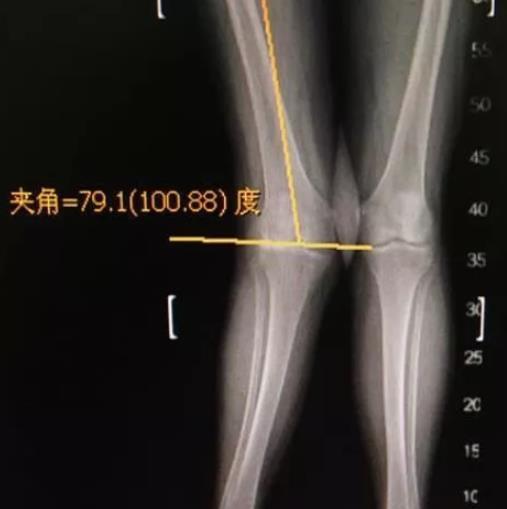

股骨远端闭合截骨(dfo)治疗严重膝外翻畸形 - 好大夫在线

图片尺寸722x315